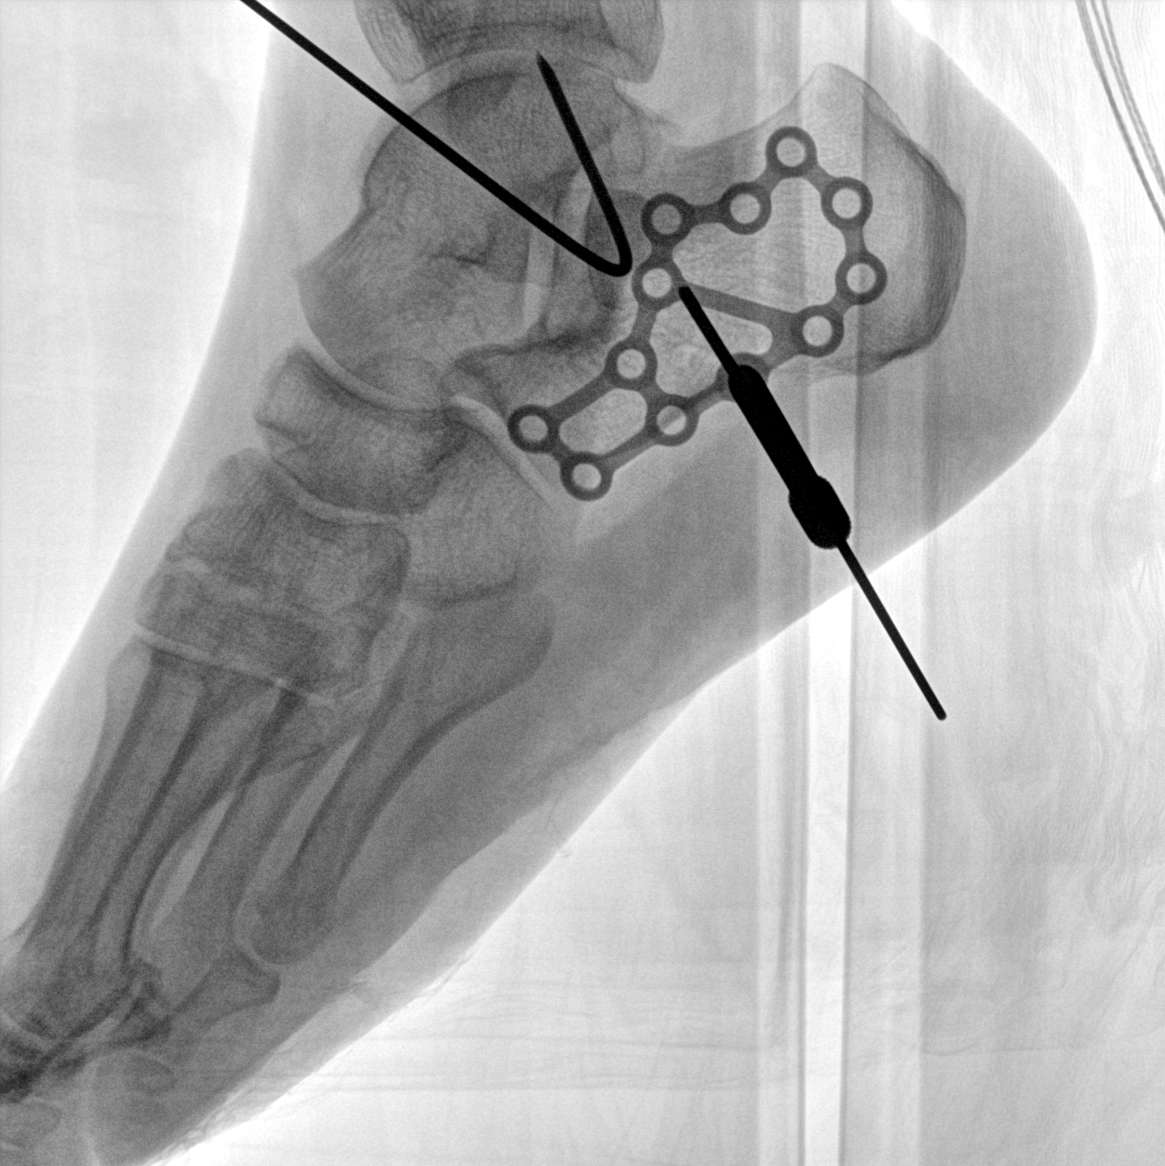

術(shù)中三維成像和橫斷面圖像提供多角度的手術(shù)診斷信息,輔助醫(yī)生進(jìn)行術(shù)中評(píng)估判斷,諸如骨折復(fù)位情況和內(nèi)植入螺釘?shù)某叽绾臀恢?,輔助手術(shù)更好地完成。

提供更大的術(shù)中三維成像視野,采集更多圖像信息,可一次拍全全段頸椎、全段腰椎、七節(jié)胸椎、雙側(cè)骶髂關(guān)節(jié)、股骨頭及單側(cè)盆骨。